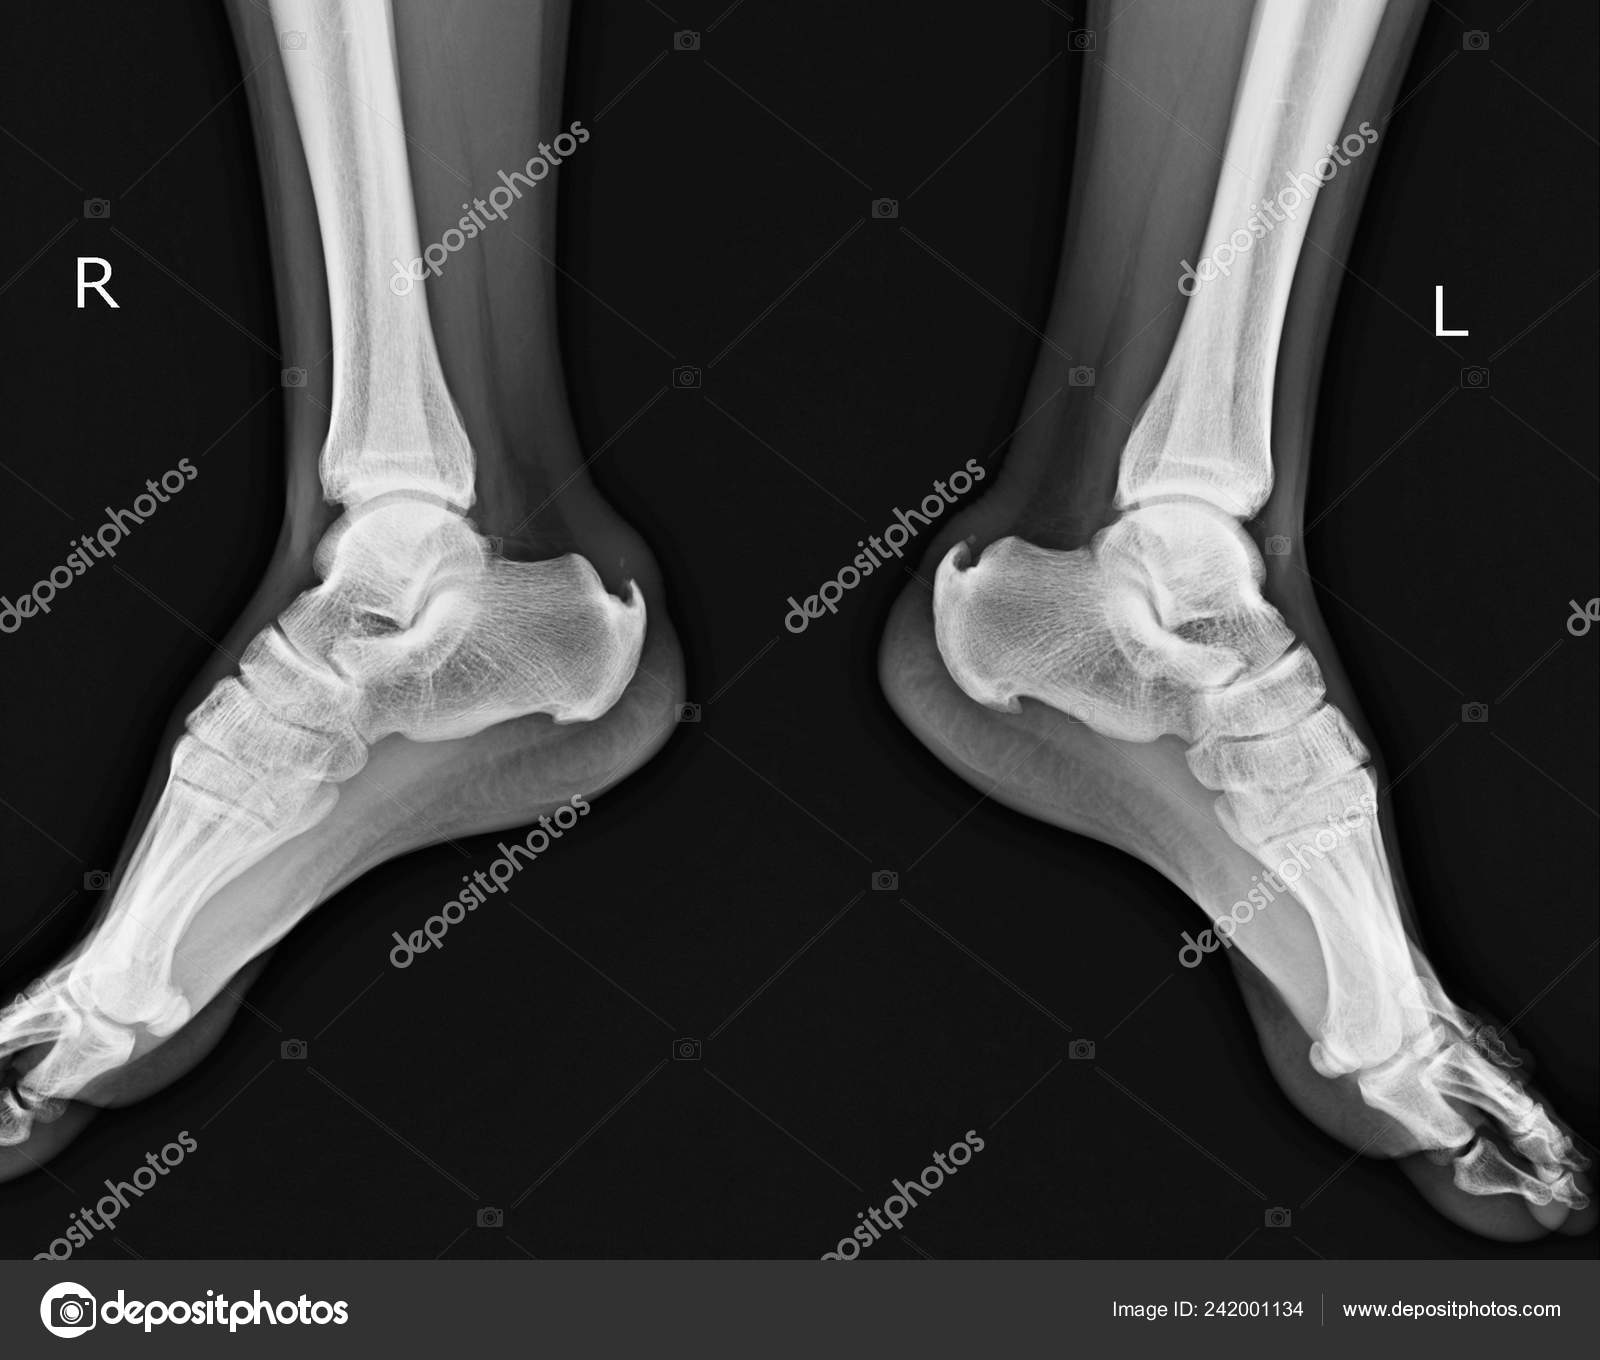

Пяточная шпора на рентгене . По рентгену пяточная шпора определяется в виде костного нароста, остеофита, который внешне выглядит как крючковидное разрастание на поверхности пяточного бугра .

Пяточная шпора — воспалительно-дегенеративный процесс, охватывающий мягкие ткани вокруг пяточного бугра . По этой причине, при облучении исследуемого участка стопы, пяточная шпора на рентгене видна отчётливо . . .

В статье вы узнаете, как выглядит пяточная шпора на рентгеновском снимке . Мы покажем фото рентген-снимка пяточной шпоры и расскажем, какое описание делает врач

Как выглядит пяточная шпора на снимке: фото . Во многом от того, как выглядит на снимке пяточная шпора, зависит назначаемое лечение .